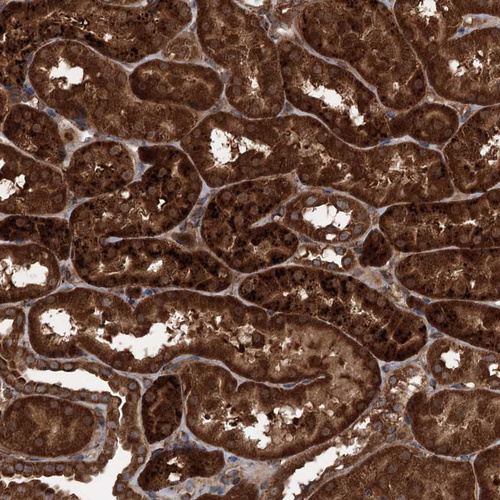

Immunohistochemical staining of human pancreas shows strong cytoplasmic-membranous positivity in exocrine glandular cells.